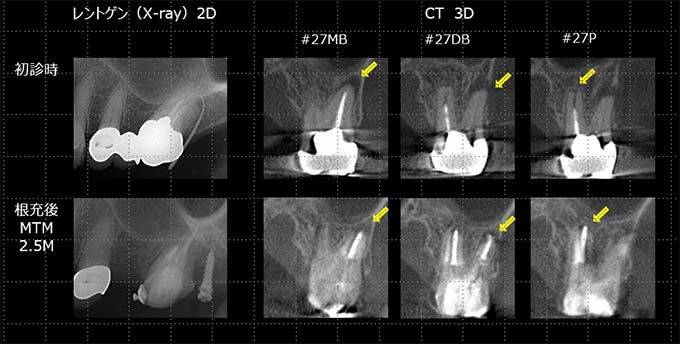

当院での治療例です。ご来院された(初診時)治療前の状態と根充後(治療後)の状態をレントゲンとCTで確認すると次のようになります。

しっかりと根充されていることがCTにより確認すことができます。